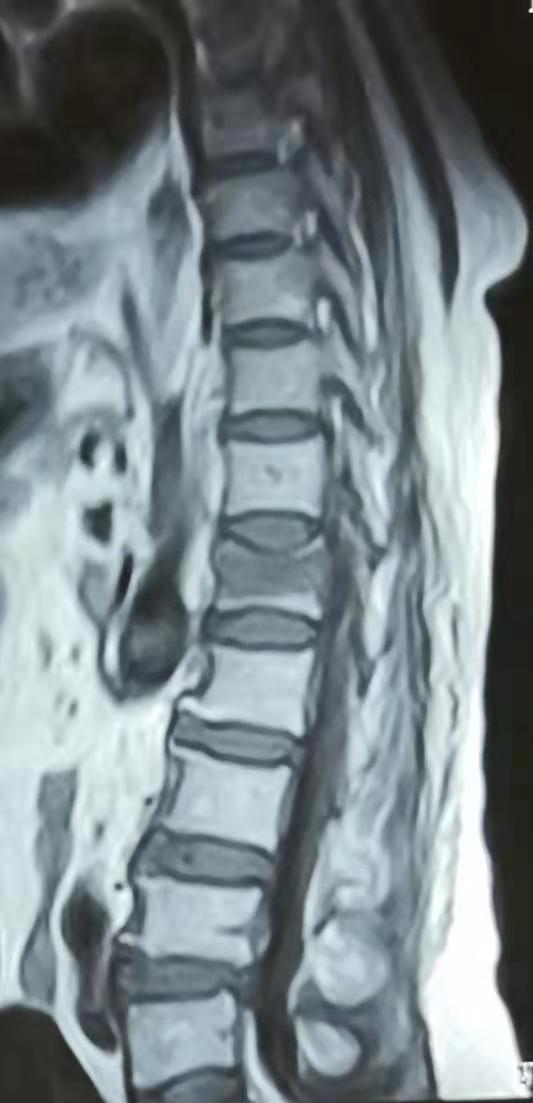

今天医院收到一位腰椎骨折的患者,还伴随有长期腰痛胸痛和消化不良,外院诊断为腰椎单纯骨折并胸部巨大脂肪瘤。在我院高档CT、磁共振的检查下,却是另外一种发现。

我们的设备,清楚地显示出外院照片没有发现的细节。

单纯腰椎骨折的背后,还发现了一个被压碎的血管瘤。而且其余椎体还有几个小的血管瘤。这就不是单纯骨折,而是病理性骨折。符合患者在轻微运动下就发生骨折的事实。